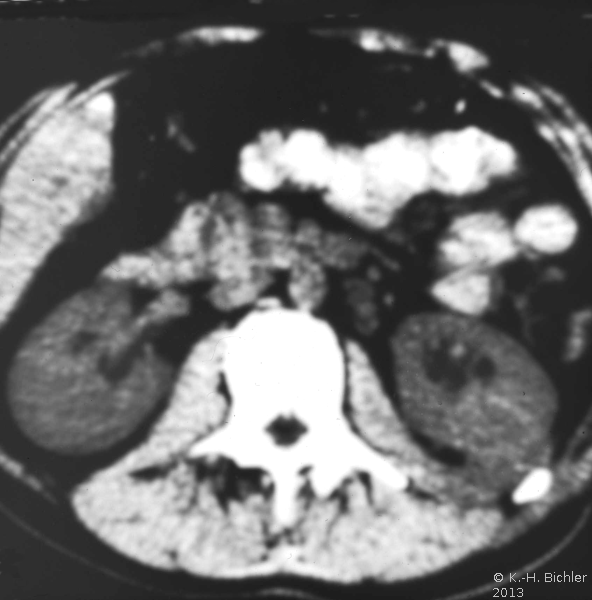

In der Diagnostik der Nierenabszesse (intra- bzw. peri/paranephritisch) spielen neben der Anamnese, Symptomatik (Fieber, Flankenschmerzen) die Laboruntersuchungen: Entzündungsparameter wie BSG und CRP, Kreatinin und Elektrolyte sowie der Urinstatus eine Rolle.

Von Wichtigkeit sind die bildgebenden Verfahren: Sonographie, CT bzw. AUR.

Beispielhaft die Darstellung eines ausgedehnten Nierenabszesses in Sonographie, CT und AUR (Abbildung 6).